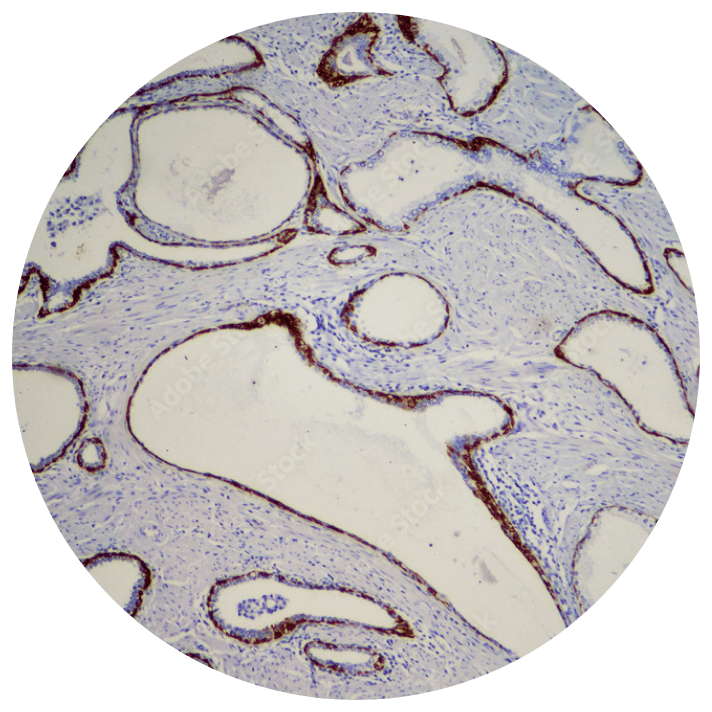

We are continually refining and adding new assays to our robust menu of more than 500 tests, including immunohistochemistry (IHC), fluorescence in situ hybridization (FISH), flow cytometry, cytogenetics, molecular, and next-generation sequencing (NGS) panels, to keep our test menu at the forefront of cancer diagnostics.